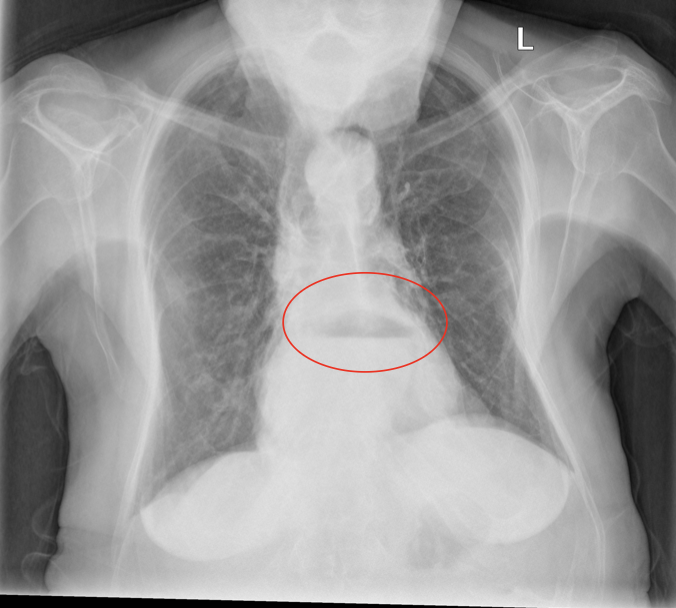

Pathology?

Hiatus hernia (stomach herniates through oesophageal hiatus)